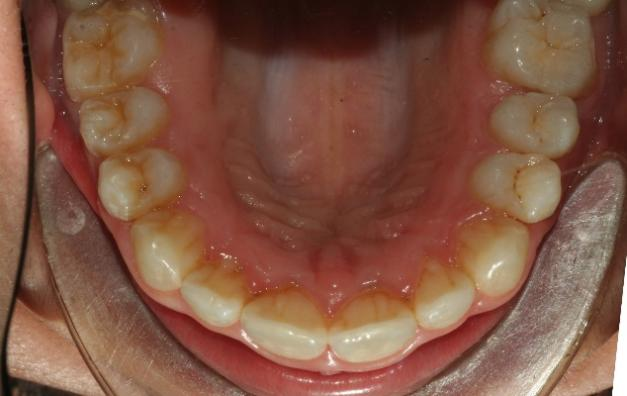

The patient in this case is a 15-year-old female who presented with mild third skeletal class with upper and lower tooth crowding at the beginning of the treatment. The whole process lasted for around 20 months employing traditional metal brackets.

Fig 1,2,3: the intraoral condition before orthodontics treatment & Fig 4,5,6: the intraoral condition after orthodontics treatment.